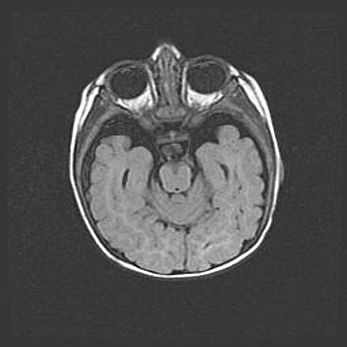

Церебральная ишемия II.

Возраст: 5 дней

Вес: 3400 г

Пол: женский

Окружность головы: 35 см

Срок гестации: 39 недель

Церебральная ишемия – это заболевание, характеризующееся недостаточностью (гипоксией) либо полным прекращением (аноксией) снабжения мозга кислородом по причине закупорки одного или нескольких сосудов. Это приводит к  что метаболическим расстройствам различной степени тяжести в тканях головного мозга, развитию коагуляционных некрозов и гибели нейронов.